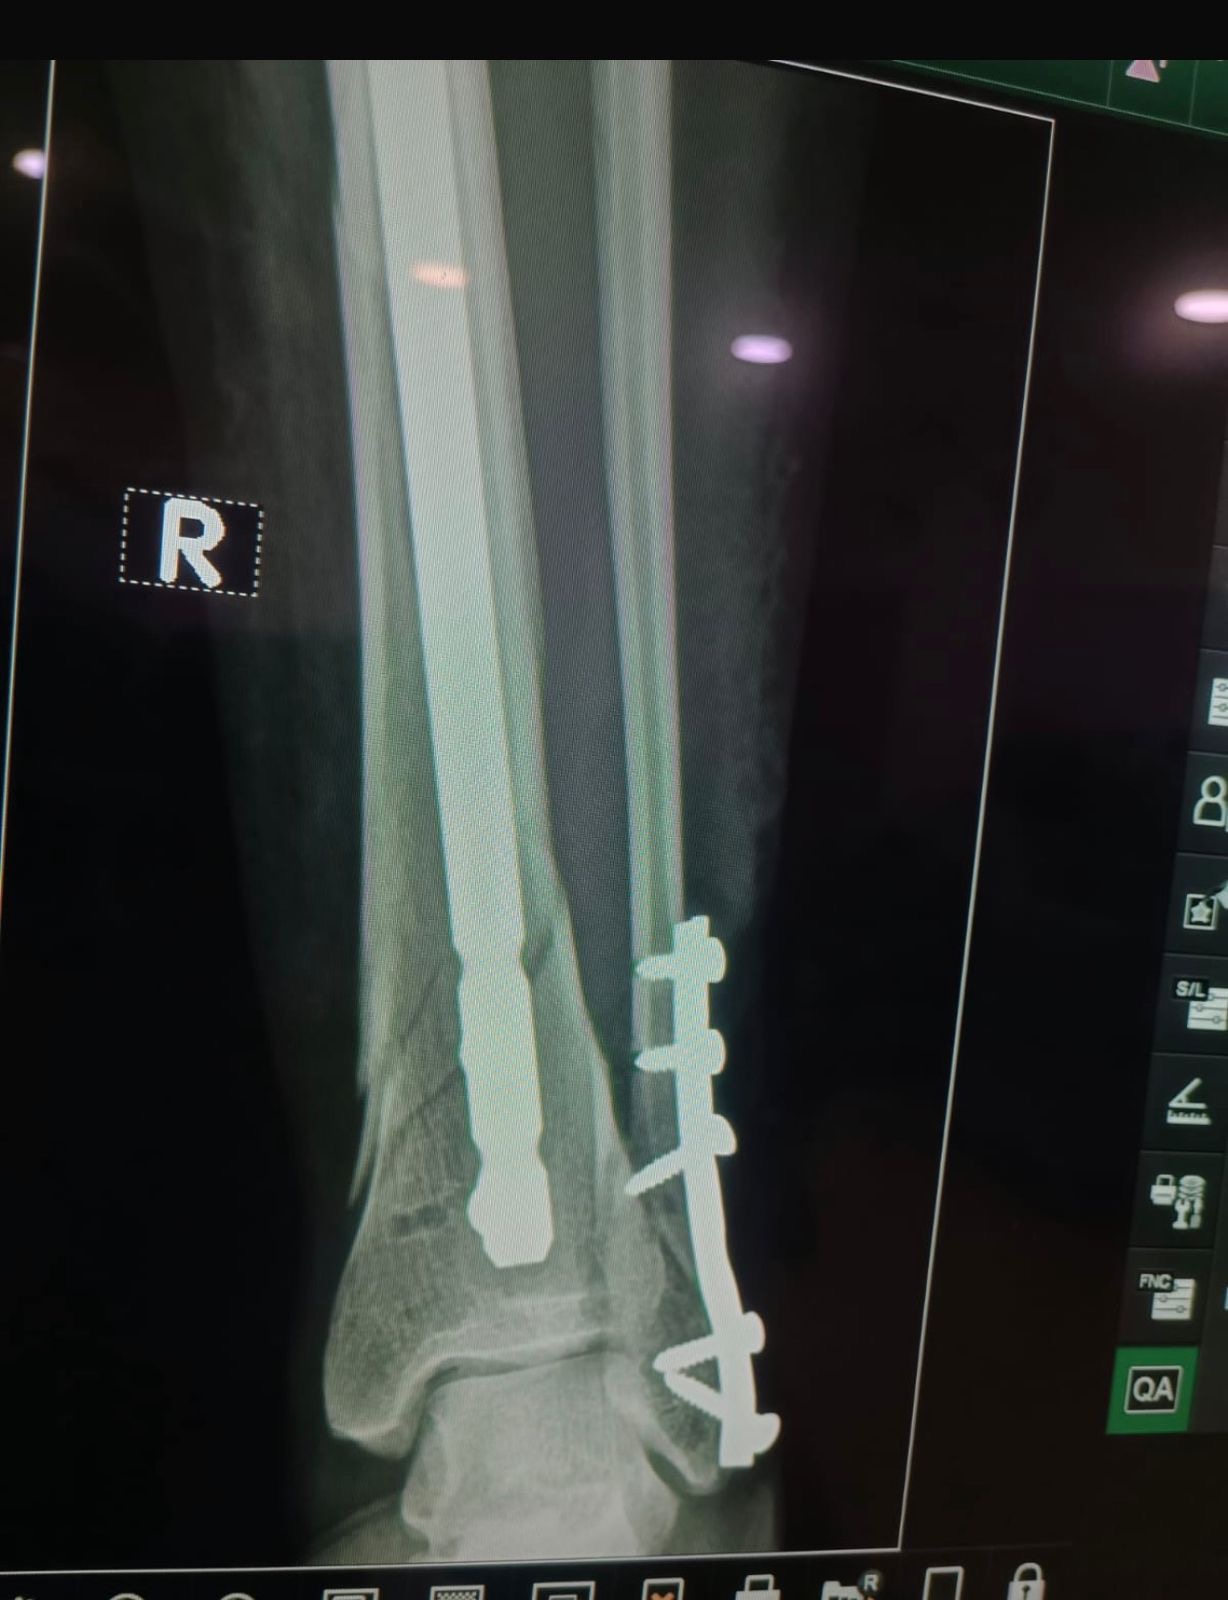

Hola soy Leonor Valenzuela, recientemente acabo de ser mamá de un niño que apenas cumplió un mes. Desafortunadamente tuve un accidente en casa que resultó en una fractura fuerte de tibia y peroné donde se me tuvo que poner dos placas de titanio y 4 clavos. Los gastos recientes de la cirugía salieron mucho más elevados de lo que esperábamos. Aprecio cada donativo que se pueda dar, es de muchísima ayuda para mi y mi familia.